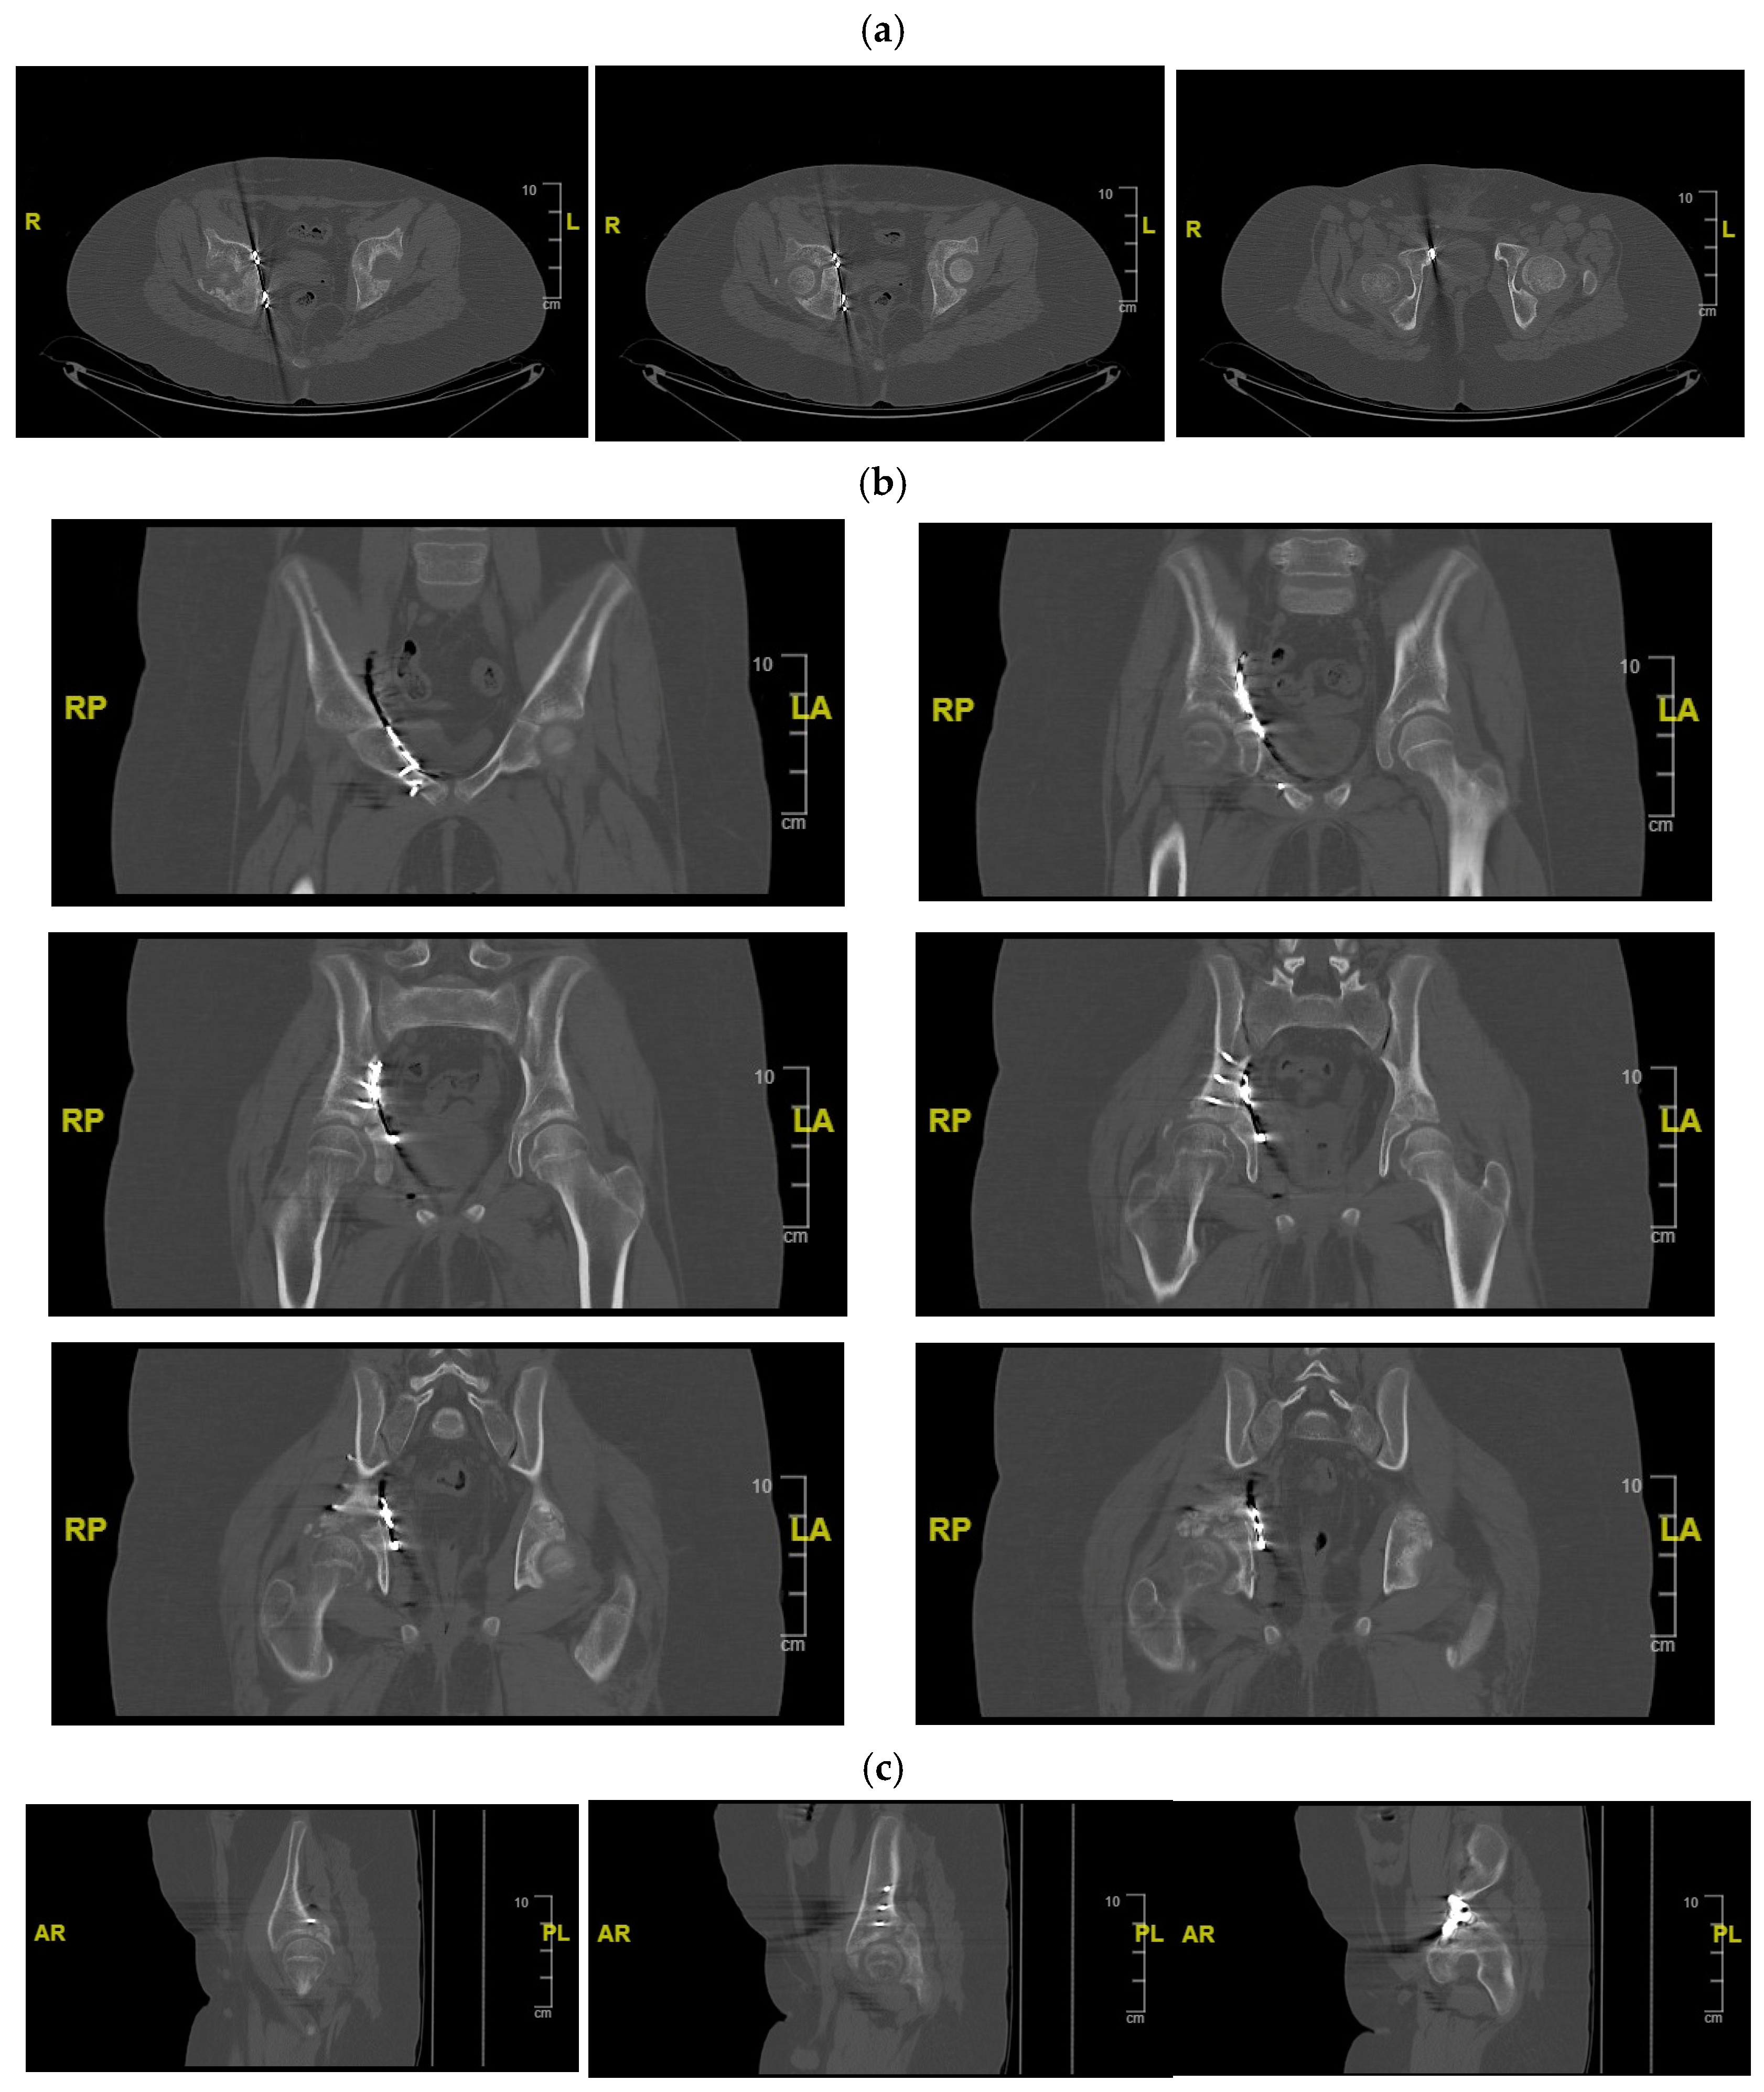

Figure 3.

CT of the pelvis showing the right acetabular fracture. (a) Axial view; (b) sagittal view; (c) coronal view. R = right; L = left; A = anterior; P = posterior.

Definitive management of the acetabular fracture was deferred until the patient’s general condition was optimised and soft-tissue status allowed surgery. A CT scan with multiplanar and 3D reconstructions of the pelvis confirmed a transverse acetabular fracture involving the triradiate cartilage on the right side, with displacement of the quadrilateral surface and medialisation of the femoral head relative to the hemipelvis.